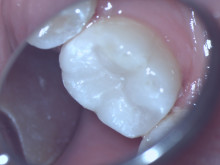

当医院での奥歯のセラミック治療は従来のセラミックより強度のあるジルコニアでおこないます。

当院では、虫歯を綺麗に取り除き、一日で制度の良いセラミックの詰め物を創ることができます。

マイクロスコープ、ラバーダム、口腔内スキャンCAD/CAMそして個別診療によりこの治療が可能です。